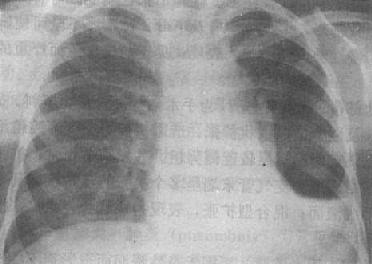

中量积液:液体量较多时,由于液体的重力作用而积聚于胸腔下部的肺四周,表现为下肺野均匀致密,肋膈角完全消失。膈影不清(图3-1-14)。由液体形成的致密影的上缘呈外高内低的斜形弧线。此弧线的形成是由于胸腔内的负压状态、液体的重力、肺组织的弹性、液体的表面张力等作用所致。实际上液体的上缘是等高,但液体的厚度是上薄下厚,液体包绕肺的周围,当摄影时,胸腔外侧处于切线位,该部液体厚度最大,因而形成外侧和下部密度高,内侧和上部密度低。

右侧胸腔中量积液

图3-1-14 右侧胸腔中量积液

右下肺野均匀致密,肋膈角与膈影不能分辨,

上缘模糊不清,心脏左移